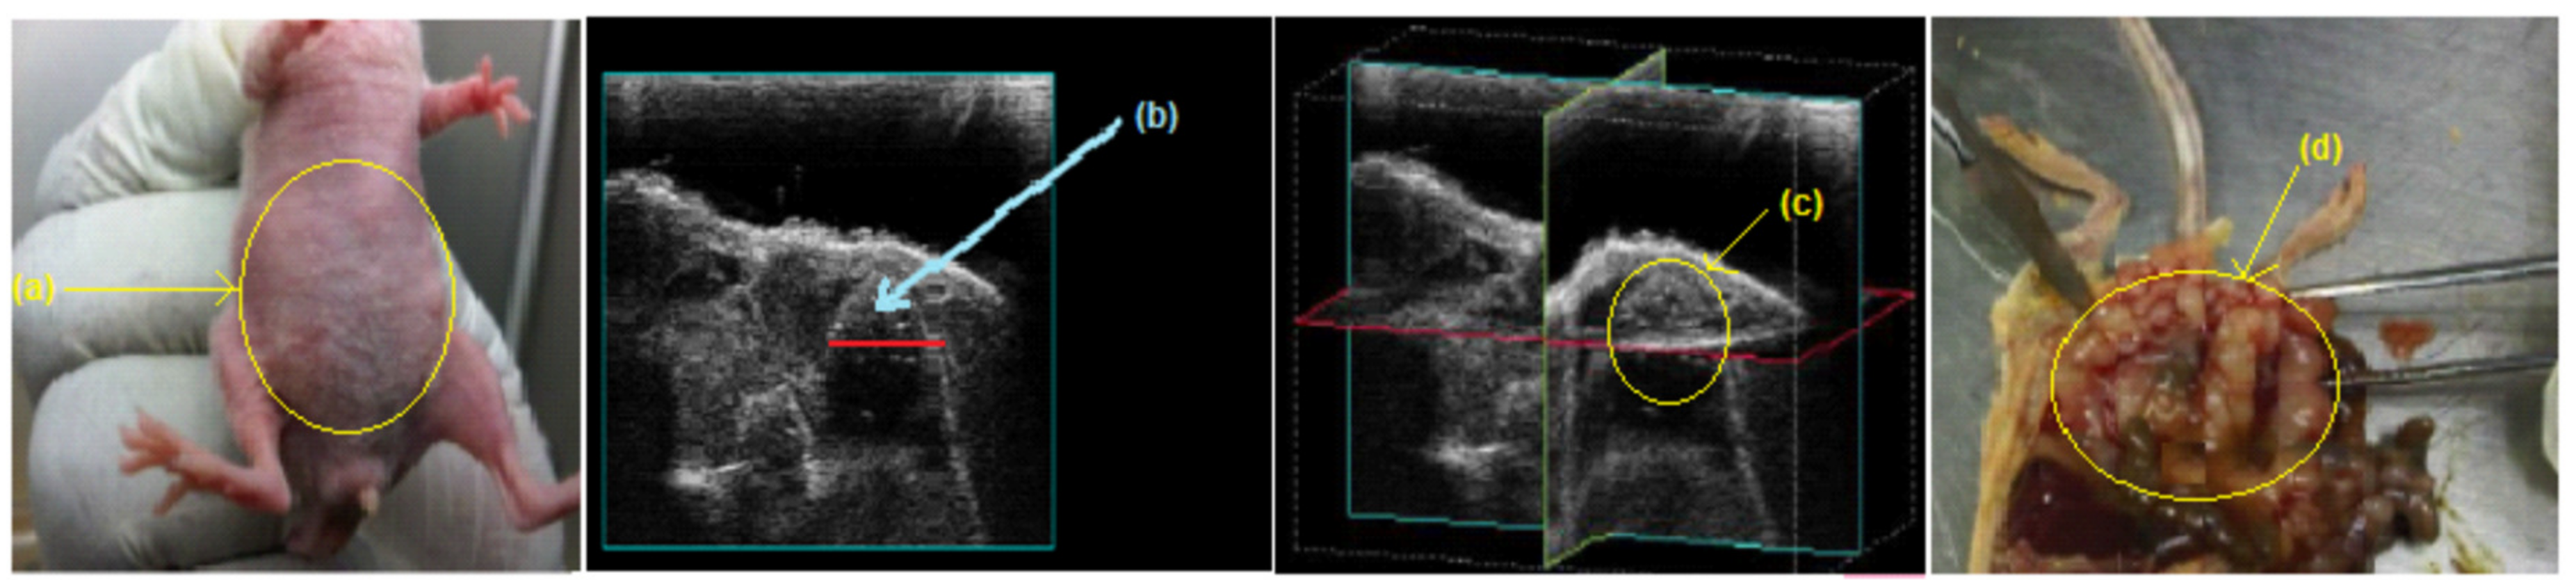

2.4.1. Induction of Human Ovarian Carcinoma in Athymic Swiss Nude Mice

4.5.4. IP-Inoculated Mice